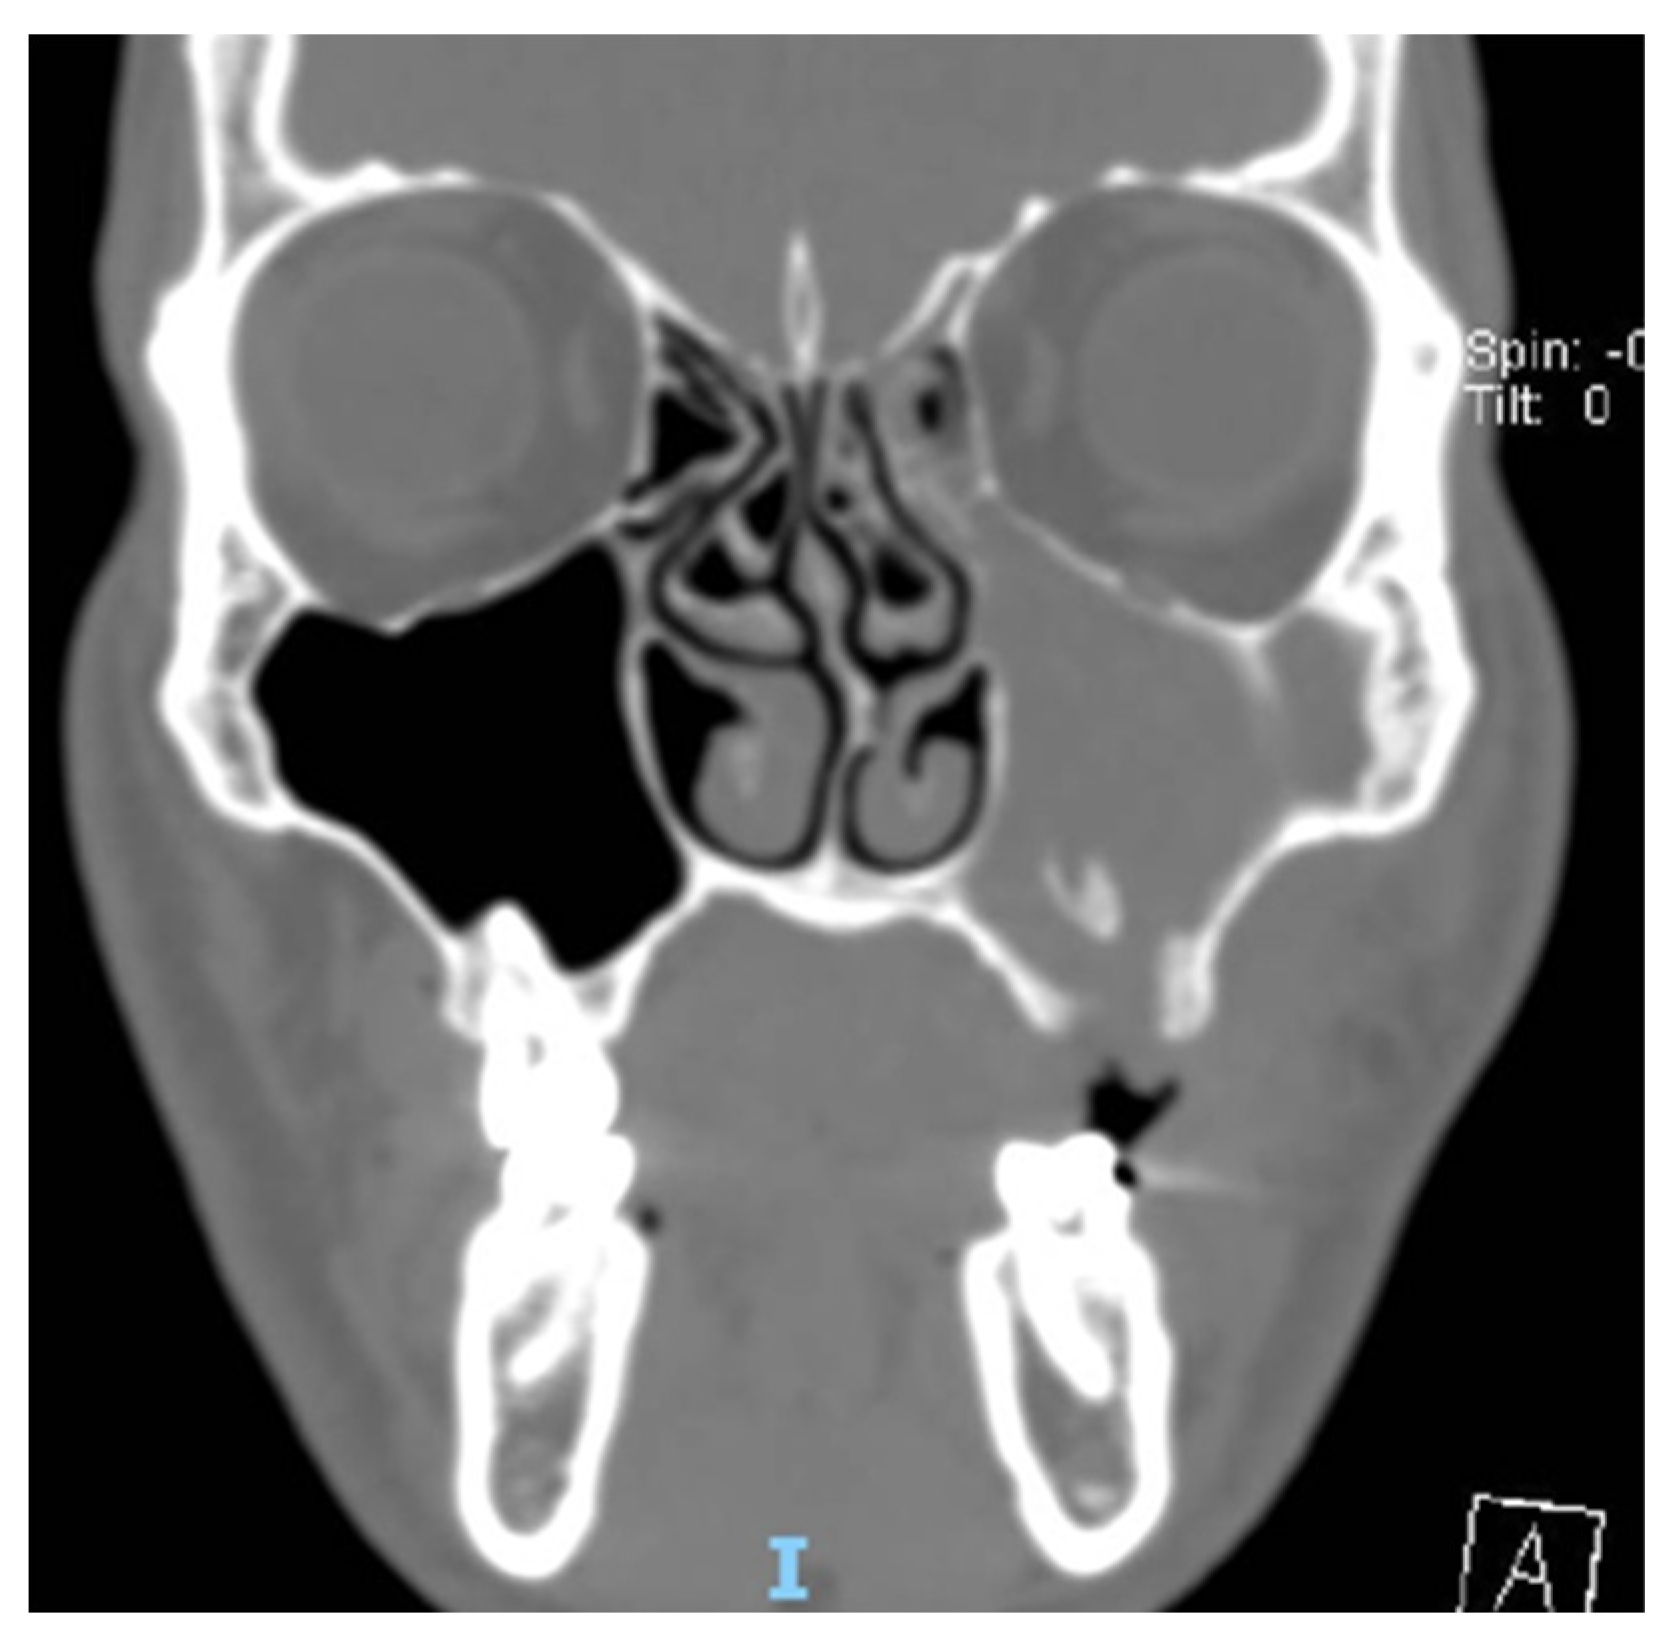

A total of 68 patients responded to the criteria and to the definition as classical odontogenic complications and were included in this retrospective study; of these, 40 were men (59.7%) and 27 were women (40.3%). The mean age was 45.8 years, (the youngest patient was 33 and the oldest 68). All the patients reported a history of previous dental disease or treatment, and the dental origin of the sinusitis was confirmed by anamnestic record, clinical observation, and radiological evidence. Maxillary pain, nasal obstruction, and an anterior or posterior nasal drip were the most referred symptoms. All patients were resistant to medical therapy. All patients underwent a head CT scan before the intervention. All patients had unilateral sinus opacification. A total of 30 patients (42%) reported an obstruction of the osteo-meatal complex (OMC). A foreign body in the maxillary sinus was found in 9 patients (13%) (Figure 1) and an OAC was present in 27 patients (40%) (Figure 2, Figure 3 and Figure 4). The surgical therapy consisted of a combined oral and nasal simultaneous approach for 28 patients (43%), a combined non-simultaneous approach for 4 patients (6%), a nasal only approach for 14 patients (21%), and an oral only approach for 20 patients (30%) (Figure 5).

Figure 4. TC exam of patient with OAF and foreign body in maxillary sinus body in maxillary sinus.